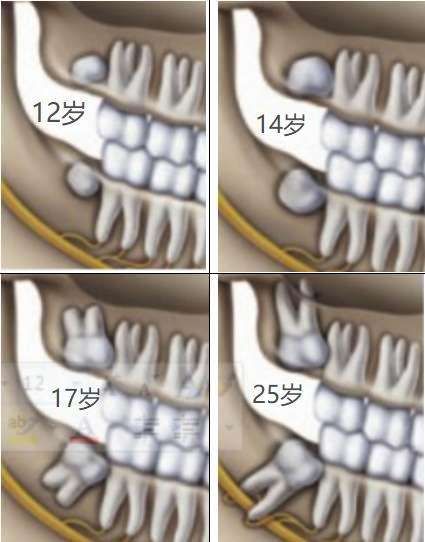

建议14~ 20岁之间拔除,原因如下:

1. 20岁以后牙根已逐渐形成,会压迫下牙槽神经,损伤下牙槽神经几率大;

2. 20以后智齿牙根发育完成,拔牙阻力增加,拔出相对困难,术后疼痛肿胀会相应加剧;

3. 20岁以后发育完成的牙根可能存在变异,多根,弯根,这就增加了拔牙难度;

4. 20以前,牙齿周围的骨质疏松,阻力小,容易拔出;

5. 年轻时拔除智齿,身体好,拔牙后反应轻,恢复快;

拔牙后注意事项: